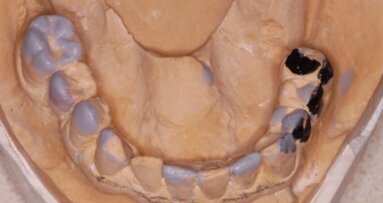

Zdecydowano o zastosowaniu protokołu DIEM, który umożliwia dostarczenie natychmiastowych mostów na 4 implantach. Podobnie, jak w przypadku innych procedur implantologicznych, technika DIEM wymaga starannego planowania. Przeprowadzono analizę estetyczną uśmiechu z uwzględnieniem pozycji wyrostka zębodołowego szczęki do wargi górnej oraz analizę warunków kostnych na podstawie badania CT.

Po usunięciu zębów wykonano nacięcie na grzbiecie wyrostka zębodołowego, odwarstwiono pełny płat, oczyszczono dokładnie zębodoły i wyrównano brzeg kości. Założono 2 implanty pionowo w obszarze przednim i 2 dystalne pod kątem, ze stabilnością początkową umożliwiającą obciążenie natychmiastowe. Dobrane zostały i przykręcone do implantów odpowiednie łączniki niskoprolowe (Low Profile Abutments). Następnie przymocowano cylindry tymczasowe i wcześniej przygotowane ruchome protezy przerobiono na prowizoryczne stałe mosty.

Koncept DIEM, polegający na użyciu 2 implantów prostych i 2 kątowych, pozwala na osadzenie stałej protezy tylko na 4 implantach. Pochylenie dystalnych implantów umożliwia lepsze rozmieszczenie głów implantów na wyrostku zębodołowym i korzystniejsze rozłożenie sił, dzięki czemu proteza (most) może mieć nawet 12 zębów.